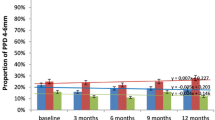

PD reduction was significantly greater in deep pockets as compared to shallow-moderate pockets at 3 and 6 months only in the test group (Table 3). Furthermore, deep pockets showed a significantly higher mean PD reduction in the test compared to the control group at 6 months. The percentage of closed pockets (PD ≤ 4 mm and BOP-) was significantly greater in the test group at 6 months when taking into consideration all sites together and the initial deep pockets sub-group (Table 4).

Bacterial species levels showed heterogeneous behaviour from baseline to the follow-up visits (Fig. 2). Some, such as Prevotella nigrescens and Prevotella intermedia, showed low levels already at baseline, which remained stable at the subsequent time points irrespective of the treatment group. Other species, such as Porphyromonas gingivalis (P.g.) and Campylobacter rectus, showed moderately high concentrations at baseline and were slightly but not significantly reduced after treatment similarly in both groups. On the other hand, Aggregatibacter actinomycetemcomitans (A.a) and Parvimonas micra (P.m.) showed high concentrations at baseline in both groups and underwent a significant reduction after treatment at the 3- and 6-month follow-ups. These reductions in A.a and P.m. were significantly greater in the test group only at 3 months.

Microbiological results. DNA level of microbial species in test (a) and control (b) groups at baseline, 3 and 6 months. Statistically significant differences evaluated by the Mann–Whitney U test. P.g., Porphyromonas gingivalis; P.m., Parvimonas micra; C.r., Campylobacter rectus; P.i., Prevotella intermedia; P.n., Prevotella nigrescens; A.a., Aggregatibacter actinomycetemcomitans. * = p < 0.05